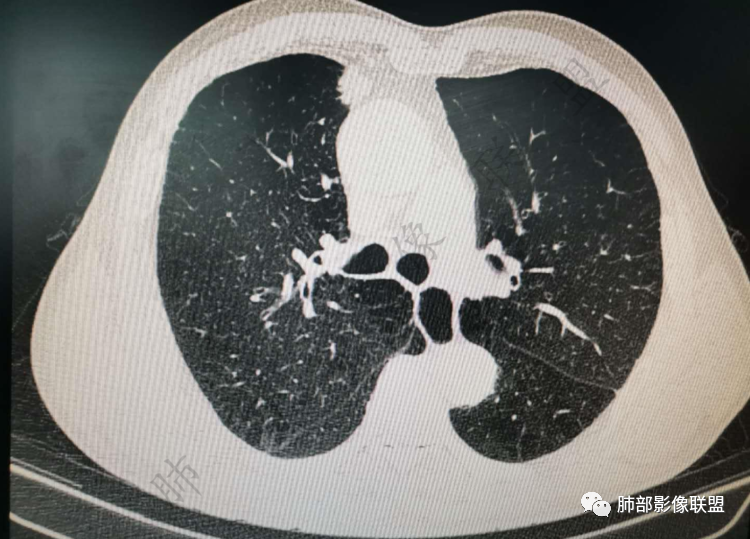

右肺上类圆形叶结节,周边见细软毛刺,增强后呈环形明显强化,内部坏死,邻近胸膜光滑,结合病史2个月明显增大,考虑炎性可能性大。

老年男性,炎性指标略高,肺气肿背景。右肺上叶胸膜下结节,部分边缘平直,部分稍模糊,软长毛刺,血管增粗,病灶中心密度减低,邻近脂肪间隙清晰。考虑炎性肉芽肿或慢性炎症,鉴别鳞癌。

老年男性,炎性指标略高,肺气肿背景。右肺上叶胸膜下结节,部分边缘平直,部分稍膨隆,供血血管增粗,增强扫描病灶中心密度减低,呈环形强化,邻近脂肪间隙清晰。考虑炎性肉芽肿或慢性炎症,鉴别鳞癌。

肺气肿背景

实性有隆起的小结节,内部有坏死、周围包括内乳动脉有增粗

病史提到有明显增大(现在看上去也不算太大,所以是不是明显增大存疑)

综合考虑还是鳞癌可能大

右肺上叶前段胸膜下结节,边缘分叶毛刺,血管集束,支气管截断,纵膈胸膜牵拉,内乳动脉增粗,密度不均,中央可见坏死,两个月短期随访结节有增大,考虑恶性,腺癌。鉴别结核。

肺气肿背景,右肺上叶纵隔旁胸膜下结节,有血管集束,支气管堵塞,内乳动脉增粗,增强不均匀强化,内可见低密度区。考虑为恶性可能性大

老年男性,肺气肿背景,右肺上叶胸膜下弧立实性不规则结节,密度不均,其内低密度坏死影,支气管似有截断,血管集束,2月复查明显增大,考虑恶性,鳞癌可能大,鉴别炎性肉芽肿

老年男性,炎性指标略高。影像表现右肺上叶胸膜下结节,膨胀性生长部分边缘平直,边界清晰,病灶可见血管集束征,近段支气管阻断?增强扫描病灶中心密度减低,低密度区边界模糊,外围环形强化。老年性,不能排除恶性病变,周围性鳞癌,其次才考虑炎性肉芽肿或慢性炎症

老年男性患者。肺气肿 ,轻微的支气管扩张,右肺上叶前段胸膜下小结节影,轻分叶,长短不一毛刺,边界欠光整,明显的强化。考虑腺癌或鳞癌。

右上叶前段结节,肺气肿背景,血管滋养丶支气管截断,与纵隔脂肪间隙清析

定性:恶性,鳞癌

老年男性,肺气肿背景,右肺上叶前段胸膜下结节,部分边缘毛糙,血管集束增粗,支气管似有截断,胸膜牵拉,结节密度不均,两个月随访结节有增大,考虑恶性,肺癌可能;另右肺上叶后段肋胸膜区小片状类结节影,考虑炎性可能。

老年男性,有肺气肿,估计有吸烟。病灶靠近胸膜宽基底紧贴胸膜。有直边征,有U型凹陷,为良性征象,有血管集数征,小的支气管截断征,为恶性征象。病灶周围没有树芽征,似乎找不到卫星灶,没有葫芦兄弟,增强扫描病灶内有空泡,所以综合考虑恶性可能大,鳞癌和粘液腺癌鉴别。良性的话结核和隐球菌鉴别。

右肺上叶前段结节,边缘毛糙,血管进入,局部细支气管似闭塞,增强有强化,中心密度似减低,2月明显增大,肺气肿背景,首先考虑炎性结节,鳞癌增大可以很快,对比老片看看

右肺上叶前段胸膜下结节,近段支气管截断,血管伸入结节内,密度不均,同侧临近内乳动脉增粗,不均匀强化,肺气肿背景,两月明显增大,考虑低分化鳞癌,隐球菌代排

老年男性,肺气肿背景,右肺前上纵隔旁结节,边缘平直,密度均匀,伴长索条影,增强均匀轻中度强化,结合2个月结节明显增大,倍增时间短,腺癌不考虑,考虑炎性肉芽肿,鉴别炎性肌纤维母细胞瘤

老年男性,白细胞计数及CRP稍高,右肺上叶结节,两个月来有增大,部分边缘可见边界模糊的GGO,局部边缘平直、凹陷,临近胸膜增厚,内见坏死,坏死区边界未见明显壁结节,壁较厚而且均匀强化,支气管似乎有扩张然后截断,近端血管增粗明显。考虑炎性病变,脓肿?有结核病人密切接触史,注意是否为结核。有点难以理解的是为什么右侧内乳动脉增粗明显。

老年男性,无症状,炎性指标增高。肺气肿背景,右肺上叶前段结节,边缘部分平直部分澎隆,血管集束,支气管至病变边缘似截断,近端扩张。增强环形强化,中心坏死。两月内病灶增长太快,考虑炎性肉芽肿,慢性脓肿?结核?癌待排。